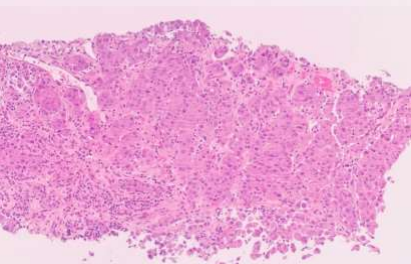

Fig.1: Iliac bone

Fig1:

- Biopsy from the right iliac bone showing metastatic carcinoma.

- The tumor cells had a single-cell pattern and were set in a stroma with a dense lymphocytic infiltrate (High TILS*). They had an epithelioid appearance, abundant eosinophilic cytoplasm, and pleomorphic nuclei with prominent nucleoli.

- They expressed epithelial markers (Pan CK, HMWCK, CK7, CK8/18, CEA) and HepPar1 (a marker of hepatocyte differentiation).

- However, Glypican 3 and AFP were negative (thus ruling out hepatocellular origin). The other negative markers were p63, SMA, Desmin, Myogenin, CD31, CD34, LCA, HMB45, S100 and CK20.

*(TILs: Tumor-infiltrating lymphocytes).

As described in figure 1, the right iliac bone showed metastatic carcinoma positive for panCK, HMWCK, CK7, CK8/18, CEA and HEPAR1 (focal).  Possible primary sites included pancreaticobiliary, upper gastrointestinal tract and lung. See the details of figure 1.